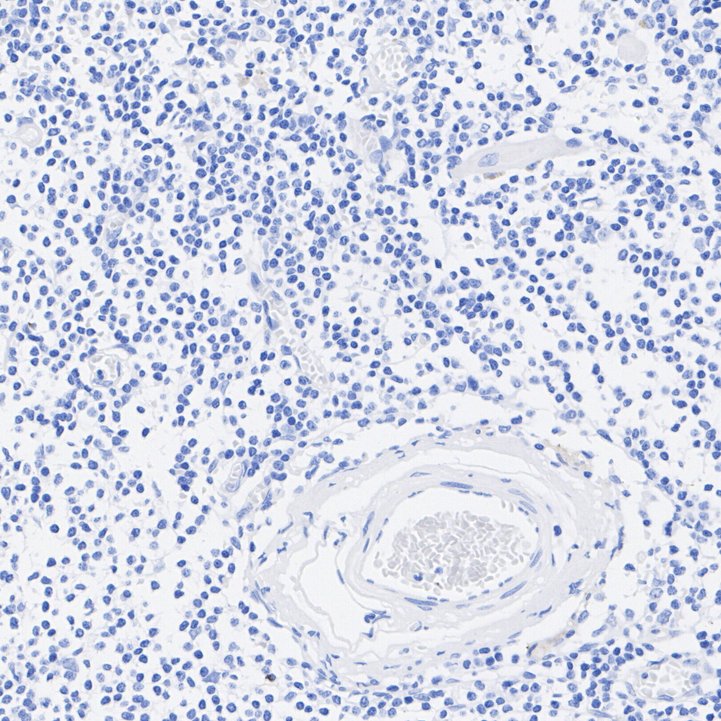

Immunohistochemical analysis of paraffin-embedded human lymph node tissue (negative) with Rabbit anti-TMEM16A antibody (HA722719) at 1/2,000 dilution.

The section was pre-treated using heat mediated antigen retrieval with Tris-EDTA buffer (pH 9.0) for 20 minutes. The tissues were blocked in 1% BSA for 20 minutes at room temperature, washed with ddH2O and PBS, and then probed with the primary antibody (HA722719) at 1/2,000 dilution for 1 hour at room temperature. The detection was performed using an HRP conjugated compact polymer system. DAB was used as the chromogen. Tissues were counterstained with hematoxylin and mounted with DPX.